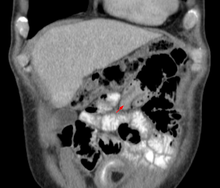

| An intussuception as seen on CT | |

An intussusception is often suspected based on history and physical exam, including observation of Dance's sign. A digital rectal examination is particularly helpful in children, as part of the intussusceptum may be felt by the finger. A definite diagnosis often requires confirmation by diagnostic imaging modalities. Ultrasound is the imaging modality of choice for diagnosis and exclusion of intussusception, due to its high accuracy and lack of radiation. The appearance of target sign (also called "doughnut sign" on a sonograph, usually around 3 cm in diameter, confirms the diagnosis. The image seen on transverse sonography or computed tomography is that of a doughnut shape, created by the hyperechoic central core of bowel and mesentery surrounded by the hypoechoic outer edematous bowel.[7] In longitudinal imaging, intussusception resembles a sandwich.[7]